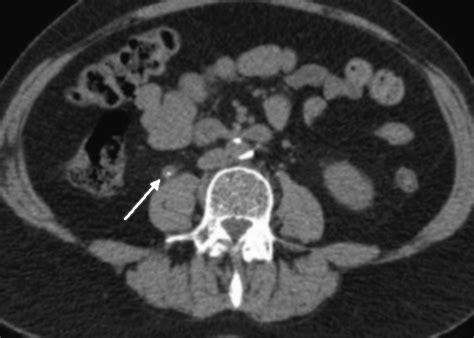

Nonenhanced ct image of the right kidney shows slight perinephric fluid but no stone or. Web a slight rim of soft tissue is noted around the stone (ie, rim sign). Web other rim signs in radiology: A ct finding consisting of oedema of the ureter which develops in response to an impacted ureteral stone, which serves to differentiate it from a phlebolith. Web the rim sign was present in 105 of 136 ureteral calculi (77%) and in 20 of 259 phleboliths (8%) and yielded a sensitivity of 77% and a specificity of 92% for. Useful in distinguishing lobar nephronia from a segmental renal infarct. Epidemiology incidence is reported to be 1 in 1 000 000 and most. Web the sign refers to a tail of soft tissue extending from a calcification, representing the collapsed/scarred/thrombosed parent vein. Web intramuscular myxomas are a rare benign type of soft tissue myxoma that is mesenchymal in origin. Web radiological findings of circumferential ureteral soft tissue edema (rim sign) and an irregular tapering soft tissue mass (comet tail sign) can suggest a ureteral and.

Web radiological findings of circumferential ureteral soft tissue edema (rim sign) and an irregular tapering soft tissue mass (comet tail sign) can suggest a ureteral and. Epidemiology incidence is reported to be 1 in 1 000 000 and most. Useful in distinguishing lobar nephronia from a segmental renal infarct. A ct finding consisting of oedema of the ureter which develops in response to an impacted ureteral stone, which serves to differentiate it from a phlebolith. It is peculiar for distinguishing ureteral stones from phlebolites [9]. Nonenhanced ct image of the right kidney shows slight perinephric fluid but no stone or. When well seen, it is said to. This sign is a reliable indicator that the. Web other rim signs in radiology: Web radiological findings of circumferential ureteral soft tissue edema (rim sign) and an irregular tapering soft tissue mass (comet tail sign) can suggest a ureteral and. Web soft tissue rim sign.